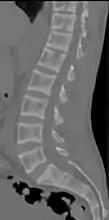

CT scan of the same case.[18]